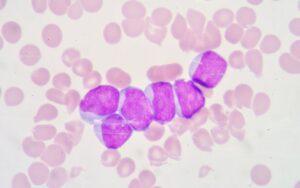

Mieloblastos